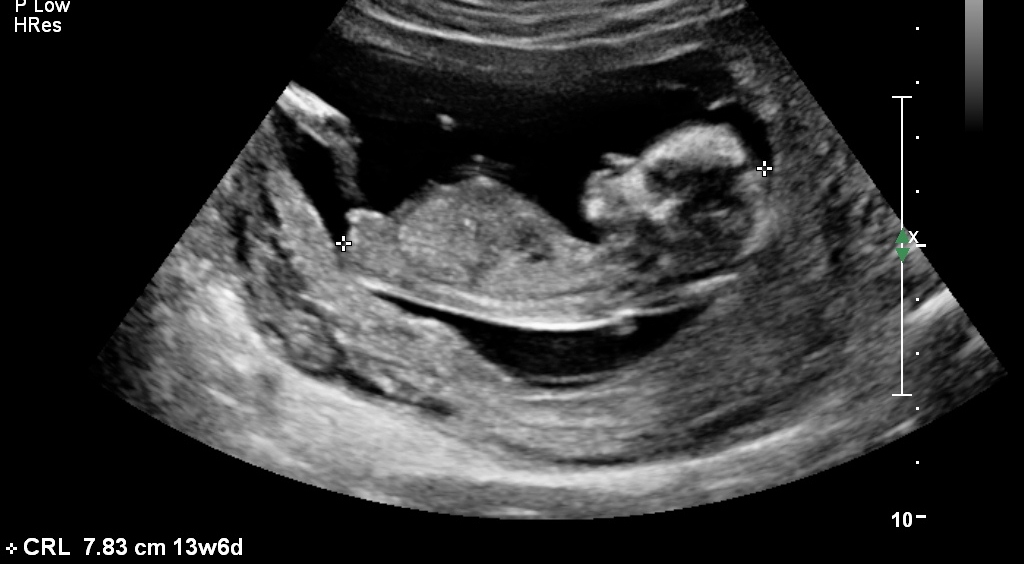

Nub is straight, girl guess!